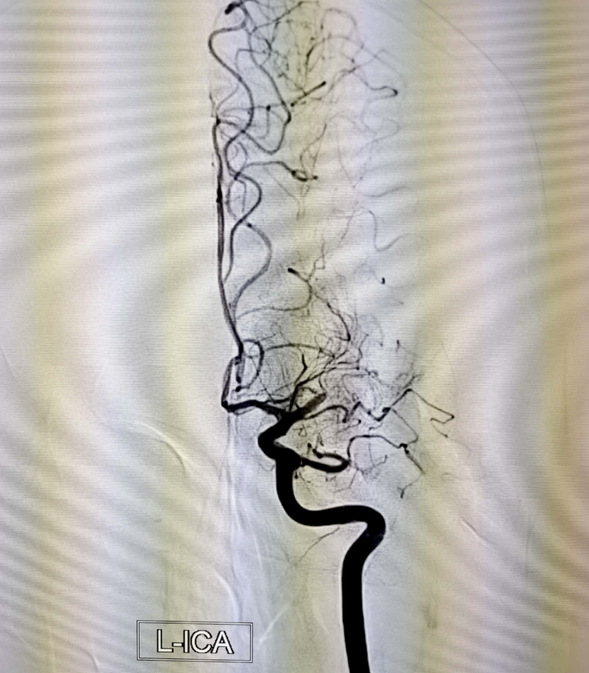

该患者男,24岁,体重95公斤,2020年4月患脑梗死病史,经过我院神经内五科治疗未留后遗症。此次患者于2022年5月22日中午12:00出现言语笨拙、右侧肢体无力,右上肢抬起费力,右下肢拖曳,约1分钟缓解,14:00再次出现上述症状,约2分钟缓解,17:00左右再次出现上述症状言语笨拙,右侧上下肢完全不能动,家长电话联系神经内五科主任迟景宏,指示急诊查头部CT及核酸,头部ct未见责任病灶,神经内五科王晓红医生及迟景宏主任查看患者:通过患者病史及入院时患者言语笨拙,右上肢肌力0级,右下肢肌力0-1级,考虑大脑中动脉栓塞,病情危重,迟景宏主任指出患者发病时间小于4.5小时可行溶栓并建议桥接取栓,于18点30分给予阿替普酶溶栓,同时请介入科评估桥接取栓,10分钟后介入科医生查看患者后,建议行脑血管造影检查必要时介入取栓治疗。患者家属同意行脑血管造影检查,王晓红医生迅给患者办理相关手续,并于18点40分前往导管室。19点55分造影结束,术中造影见左侧大脑中动脉M1段闭塞。

介入科主任刘琳与副主任莫庆国与患者家属交代病情,患者家属同意急诊取栓治疗,经商议后决定行BADDASS治疗,三件套组合:BGC+中间导管+长取栓支架,交换8F动脉鞘,引入BGC:8F×95cm;颅内支持导管:5F*125cm;取栓支架:4mm*30mm至远端病变血管,透视下释放取栓支架至病变血栓处,停留8分钟后取出大量血栓,取栓成功。复查造影见左侧经内动脉、左侧大脑前动脉、左侧大脑中动脉显影正常,血流改善,各分支显影良好,M1段未见明显狭窄,术中复查C臂CT未见颅内出血。术后患者意识清楚,问话对答切题。